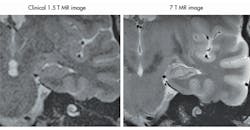

The new generation of ultra-high-field devices, with B-fields of 7 T, 9.4 T, or higher, introduces a new set of problems for MRI designers to consider. High-field devices produce images with much better resolutions than their low-field counterparts (Fig. 1).1 But they also operate at higher frequencies and produce higher power absorption in the human body; while the signal-to-noise ratio (SNR) improves linearly over frequency, the SAR is proportional to the square of the frequency, and this can increase heating effects substantially.

1. This is a comparison of the images from low- and high-field MRI systems, showing a cross-section of a hippocampus.